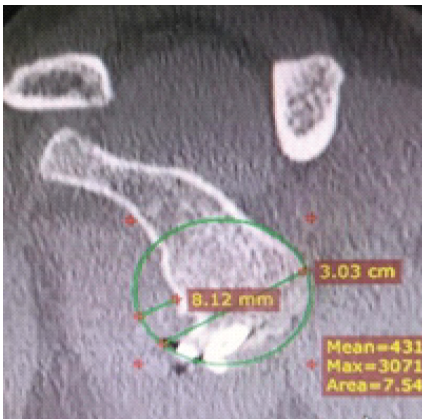

A 38-year-old male with a history of right shoulder instability in the past was managed with the Latarjet procedure 4 years ago. The patient had an uneventful post-surgical period, but symptoms recurred a year later without any significant event. He presented to us with complaints of right shoulder pain and instability since 3 years, having experienced multiple episodes of dislocations, which were managed with closed reduction at different centers. On examination, the Beighton score was five. 1 cm wasting was noted in the right arm. Sensations over the arm were intact. Tests for anterior instability, such as apprehension, relocation-release, and anterior drawer, were positive. There were no signs of instability in posterior and inferior directions. He had a nearly complete range of motion in all planes but was apprehensive to use the arm for overhead activities and lifting heavy objects. X-ray and computed tomography (CT) scan were done, which revealed a displaced as well as a broken screw near the right glenoid, likely from the previous surgery (Fig. 1 and 2). The anteroinferior part of the glenoid appeared to be resorbed. Bone loss was quantified using the perfect circle method in oblique sagittal plane, which was approximately 27% (Fig. 3). Infective etiology was ruled out via clinical examination and radiological investigations.

Figure 3: Oblique sagittal view in computed tomography scan showing approximately 27% bone loss.